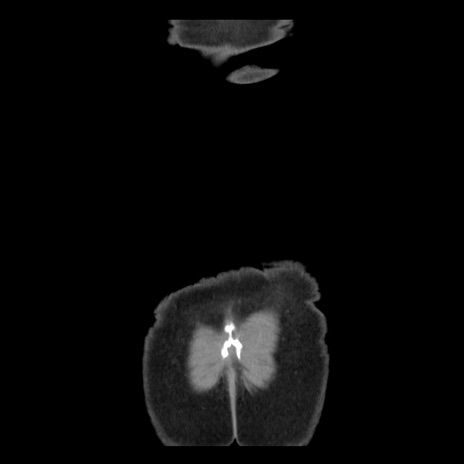

横断像

【症例】 50歳代女性

【主訴】 腹痛

【現病歴】前日生レバーを食べた。今朝に排便あり。 昼前に突然発症の腹痛を生じ、当院救急外来を受診した。

【既往歴】 子宮筋腫にてで子宮全摘後

【身体所見】 意識清明、腹部:平坦、軟、下腹部やや左を中心に圧痛・反跳痛あり、筋性防御あり

【データ】WBC 7800、CRP 0.07